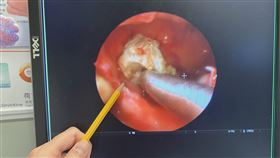

壯年男長期聞到異味 內視鏡照到這球

你是否常覺得嗅覺異常或聞到怪味?除了懷疑新冠病毒感染...

2022/04/01 11:43